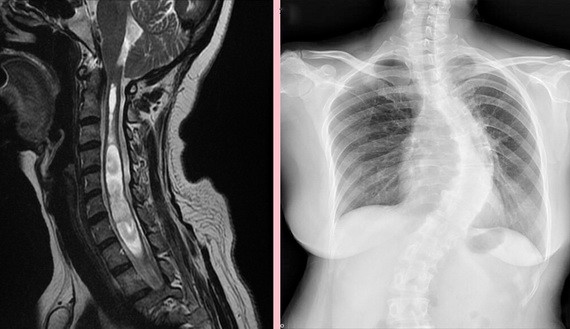

從影像學中可看出黃女士脊椎側彎角度頗大。

專家指出,經測量發現黃女士脊椎側彎角度高達63度,導致腦脊髓液流動阻塞,造成壓力差,出現脊髓空洞的情形。由於她脊髓空洞處接近右側,導致右側肢體症狀較嚴重,透過後顱窩減壓及重建腦脊髓液循環手術治療後,頭暈及左側肢體力量立即改善,右側肢體仍需要透過長期復健,才能恢復以往的功能。